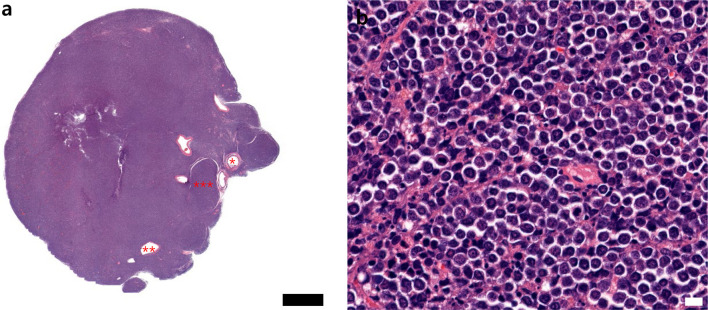

Lymphoblastic lymphoma (LBL) is an aggressive neoplasm characterized by the proliferation of undifferentiated lymphocytes. It primarily spreads to immune organs such as the thymus, spleen, lymph nodes, bone marrow, and liver. Although well-documented in humans, spontaneous LBL cases in laboratory animals are exceedingly rare. This study reports a case of T cell-derived LBL in a young adult ICR mouse, notably without bone marrow metastasis. This case provides valuable insights into the spontaneous occurrence of LBL in laboratory rodents by contributing to comparative oncology and preclinical research.